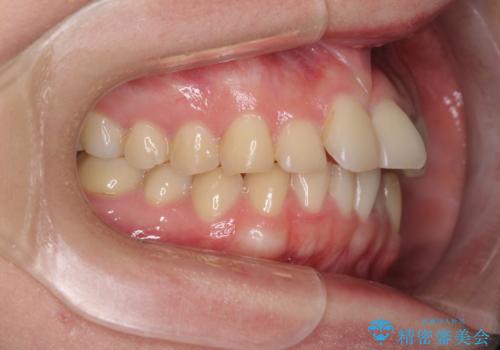

- 食いしばりが気になっていたとのことで来院された患者様です。

当初は睡眠時のマウスピースのみの製作をご希望でしたが、矯正治療の提案をしたところ、インビザラインにて矯正治療を行うこととなりました。

矯正治療中に食いしばりがより強くなることがあるため、半年に1回のペースでボツリヌストキシンによる咬合力緩和を並行して行うこととしました。

咬合力の緩和と食いしばりがちな咬み合わせが改善され、顎の負担が大幅に軽減されました。